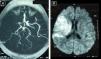

Niña de 22 meses, previamente sana, que ingresó en cuidados intensivos pediátricos con sospecha de fallo cardiaco. La ecocardiografía inicial mostró dilatación de cavidades izquierdas, contractilidad disminuida y fracción de eyección (FE) del 31%, sin trombos intracardiacos. Tras 2h de ingreso, previo a la canalización venosa central, desarrolló parálisis facial y hemiparesia izquierdas; una nueva ecocardiografía tras la canalización de la vía femoral mostró un trombo atravesando el foramen oval (fig. 1). Se realizó tomografía computarizada craneal, normal, y resonancia magnética (RM) cerebral, mostrando un extenso infarto isquémico hiperagudo en el territorio de ACM derecha (fig. 2). Se inició tratamiento inotrópico, diurético, anticoagulante, antibioterapia, gammaglobulinas, y comenzó rehabilitación precoz. El estudio etiológico (serologías, cultivos, metabólico) fue negativo. Mejoró progresivamente; ecocardiográficamente persistía dilatación cardiaca, contractilidad disminuida y FE del 31% mantenida. Permaneció 13 días en cuidados intensivos; a los 31 días fue dada de alta a domicilio (tratamiento con digoxina, furosemida, enalapril, carvedilol, heparina subcutánea, acenocumarol y levetiracetam). Controlada ambulatoriamente, recuperó marcha autónoma con ortesis 2 meses tras el ingreso; al año presentaba aceptable manejo del brazo izquierdo, sin uso funcional de la mano; a nivel cardiológico evolucionó satisfactoriamente, mostrando el último control, realizado al año, buena contractilidad miocárdica, sin dilatación cardiaca, con FE del 70%.

A) Resonancia magnética cerebral; Secuencia Tof: oclusión de arteria cerebral media derecha proximal. B) Resonancia magnética cerebral; Secuencia difusión: restricción a la difusión en el territorio de la arteria cerebral media derecha, sugestivo de infarto isquémico hiperagudo en dicho territorio.